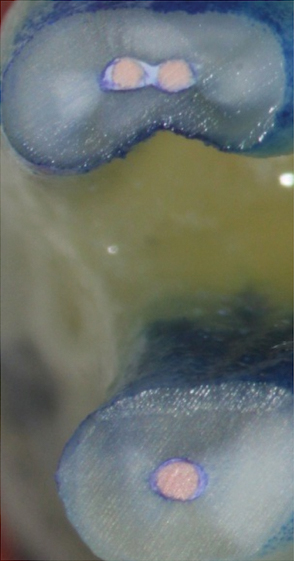

Fig 12. Postoperative radiography after full pulpotomy was performed. Courtesy of Dr. Guillaume Jouanny.

Figure 12

Fig 13. Tooth was asymptomatic at 1-year follow-up. Courtesy of Dr. Guillaume Jouanny.

Figure 13

Fig 14. Contralateral tooth at 1-year follow-up. Courtesy of Dr. Guillaume Jouanny.

Figure 14